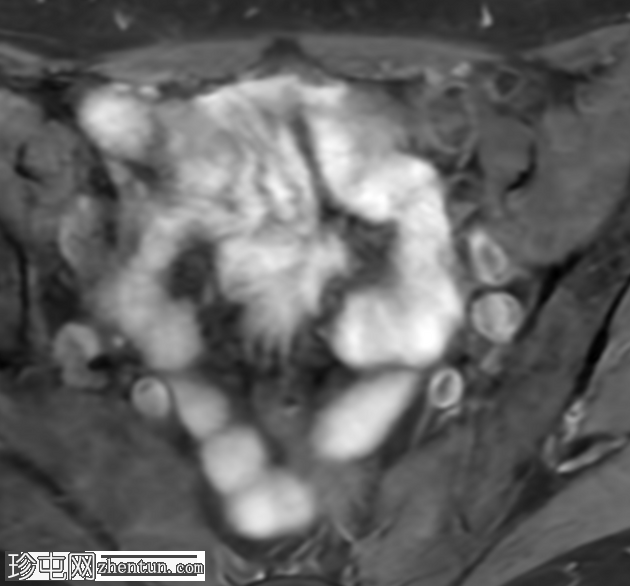

冠状位

T2加权像

盆腔MRI显示右侧卵巢解剖位置可见一边界清晰的卵圆形肿块。该病灶由囊性和实性成分组成。囊性部分壁薄,在T2加权像上呈均匀高信号,在T1加权脂肪抑制序列上呈低信号,无对比剂增强。该实性成分的信号特征与正常卵巢组织相似,DWI成像未见扩散受限,静脉注射造影剂后未见异常强化。

此外,在子宫左侧壁可见一管状薄壁囊性结构,延伸至同侧髂外血管,末端呈盲端。该结构在T2加权像上呈均匀高信号,在T1加权脂肪抑制序列上呈低信号,且无造影剂强化。

本例中,盆腔MRI显示,患者右侧卵巢解剖位置存在一个边界清晰的附件肿块,该患者有20年前行双侧输卵管卵巢切除术的病史。该病灶包含囊性和实性成分,其中实性部分表现出与正常卵巢组织相似的信号特征。无扩散受限和无可疑的增强扫描强化提示排除恶性病变。这些影像学特征结合相关的手术史进行解读,符合残留卵巢组织的特征,支持卵巢残留综合征的诊断。此外,还发现对侧子宫左侧延伸出一个管状薄壁囊性结构,末端呈盲端。其形态、信号特征和无强化表现符合输卵管残端或输卵管残端积水,这是输卵管切除术后常见的术后表现。附件残余的存在进一步支持术后病因,而非原发性妇科肿瘤